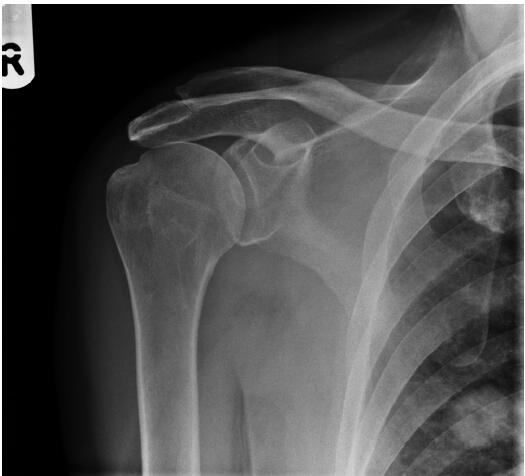

患者,男性,62歲,跌倒后,肩膀越來越疼。全科醫(yī)生要求該患者進行放射檢查(圖1)。

圖1右肩前位X光平片